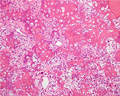

- ★(6)Osteosarcoma

X-ray finding (Left) and macroscopic view (Right): X-ray shows irregular bone destruction and sclerosis. It is concordant with macroscopic view, with destruction of cortical bone and grayish white solid tumor extending into the soft tissue.